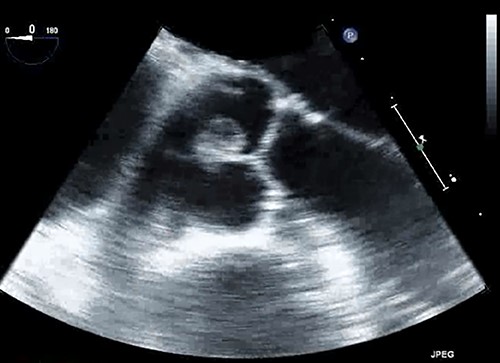

A 67-year-old male patient with past medical history of rate-controlled persistent atrial fibrillation, hypertension, hyperlipidemia and type II diabetes mellitus was scheduled for elective transcatheter ablation for treatment of atrial fibrillation. However, during pre-procedural trans-thoracic echocardiogram, a pedunculated shimmering mass measuring 16 × 8 mm was discovered on the noncoronary cusp of the aortic valve, representing a papillary fibroelastoma (Fig. 1). This finding prompted the cancellation of the transcatheter ablation and referral to cardiothoracic surgery for further evaluation. This patient had no history of embolic events or aortic insufficiency from the papillary fibroelastoma, and the only significant cardiac finding on physical examination was atrial fibrillation; it was determined that the patient was a candidate for papillary fibroelastoma resection with concomitant Cox-Maze IV procedure for treatment of atrial fibrillation.

Papillary fibroelastoma seen on trans-esophageal echocardiogram as a pedunculated mass on the aortic valve measuring 16 × 8 mm.